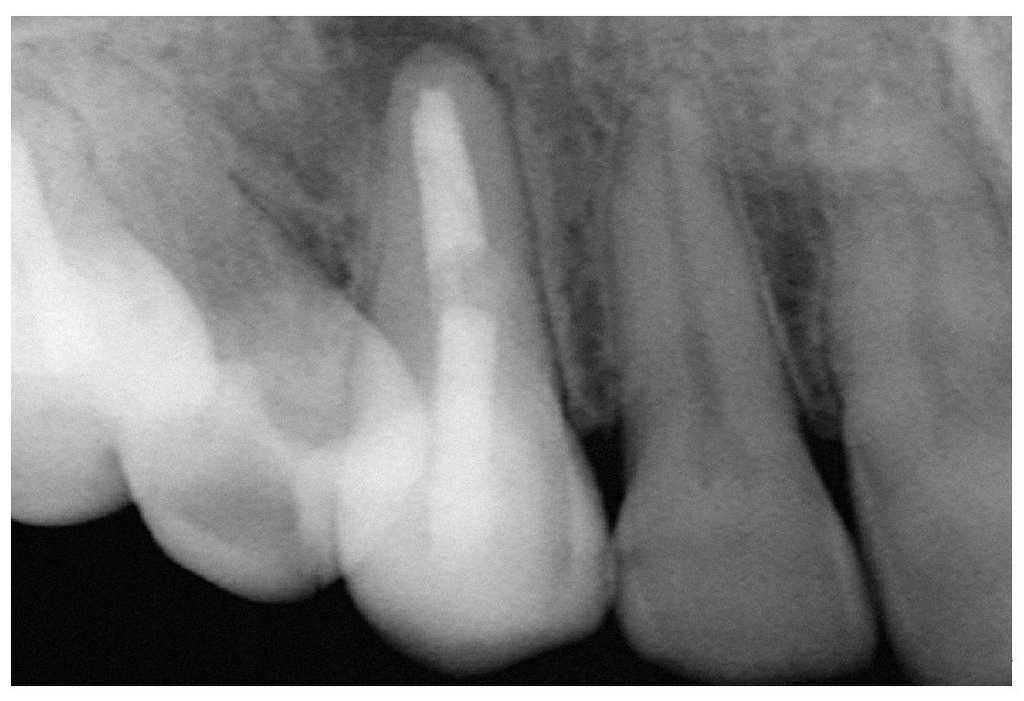

Figura 2a. Retratamiento del diente 36. Presencia de gutapercha en el conducto mesiovestibular y mesiolingual.

Figura 2b. La punta ultrasónica en contacto con la gutapercha.

Figura 2c. Eliminación de la gutapercha de la zona coronal.

Figura 2d. Resultado después del procedimiento ultrasónico.